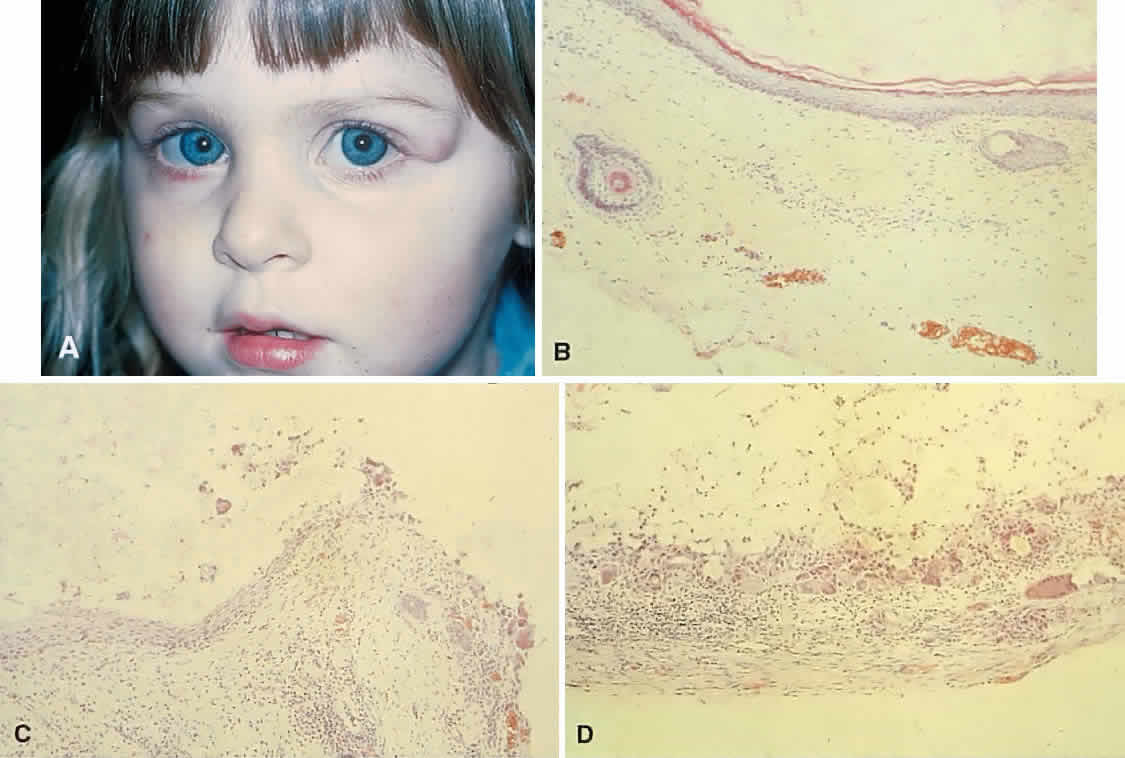

orbit. Dumbbell lesions may be present with narrow intraosseous components.  Fig. 19. A. This 2-year-old girl had a mass overlying the superotemporal orbital rim

since birth. The area had enlarged and had become red and tender in

the preceding few weeks. B. The recent clinical changes are explained by rupture of the cyst wall

and a granulomatous inflammatory response to the expelled contents. This

section shows typical stratified squamous epithelium, hair shafts in

the wall, and keratin in the lumen. C. Transitional zone between the dermoid cyst wall and an encapsulated granulomatous

response. D. The wall of the cyst beyond the point of rupture. Note the multinucleated

giant cells and fibrous capsule. (B-D, hematoxylin-eosin; × 96.) Fig. 19. A. This 2-year-old girl had a mass overlying the superotemporal orbital rim

since birth. The area had enlarged and had become red and tender in

the preceding few weeks. B. The recent clinical changes are explained by rupture of the cyst wall

and a granulomatous inflammatory response to the expelled contents. This

section shows typical stratified squamous epithelium, hair shafts in

the wall, and keratin in the lumen. C. Transitional zone between the dermoid cyst wall and an encapsulated granulomatous

response. D. The wall of the cyst beyond the point of rupture. Note the multinucleated

giant cells and fibrous capsule. (B-D, hematoxylin-eosin; × 96.)

|